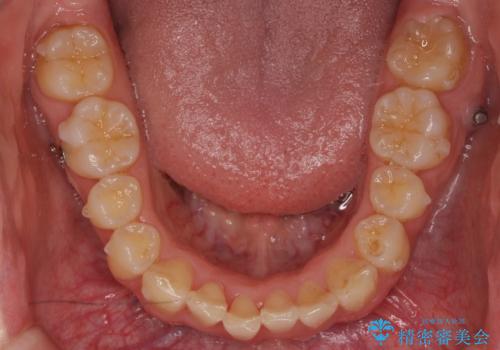

- 前歯のがたつきを主訴に来院。

左下の奥歯を後ろに移動して、中に入ってすれちがっていた小臼歯を並べました。

奥歯を後ろに移動させるために、矯正用のミニスクリューを用いました。(インプラント矯正)